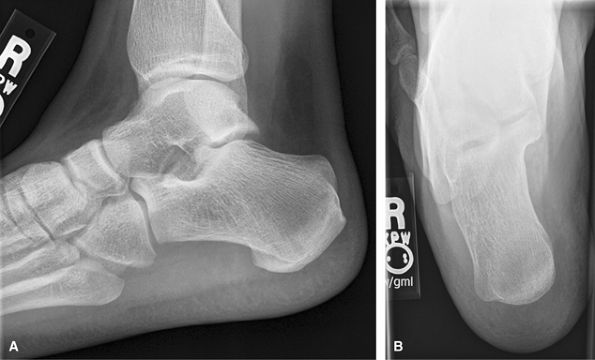

OS Calcis

Weight-bearing for alignment or non–weight-bearing for

mass or if too painful to stand. Good for trauma and heel alignment.

This should be the preferred study for heal pain rather than a foot

series. The posterior subtalar joint and middle subtalar facet are often

well visualized on the axial or Harris Beath view. Consider CT for full

preoperative assessment of calcaneal fractures.

Figure 22 (A) Lateral calcaneus mediolateral projection. (B) PA axial plantodorsal.